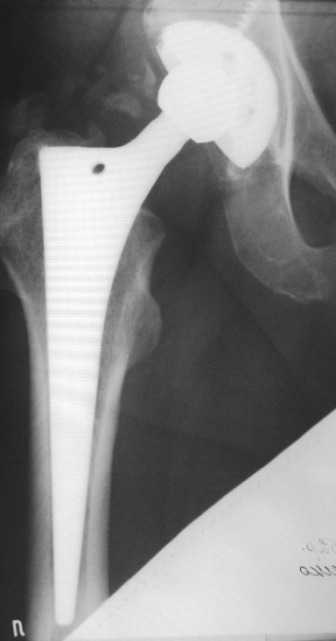

Проблема не в протезе, это очень хороший протез Трилоджи-Версис ЕТ и имеются четкие признаки остеоинтеграции. Ищите другие причины болевого синдрома - тенопатия ягодичных м-ц, остеохондроз позвоночника и т.д.